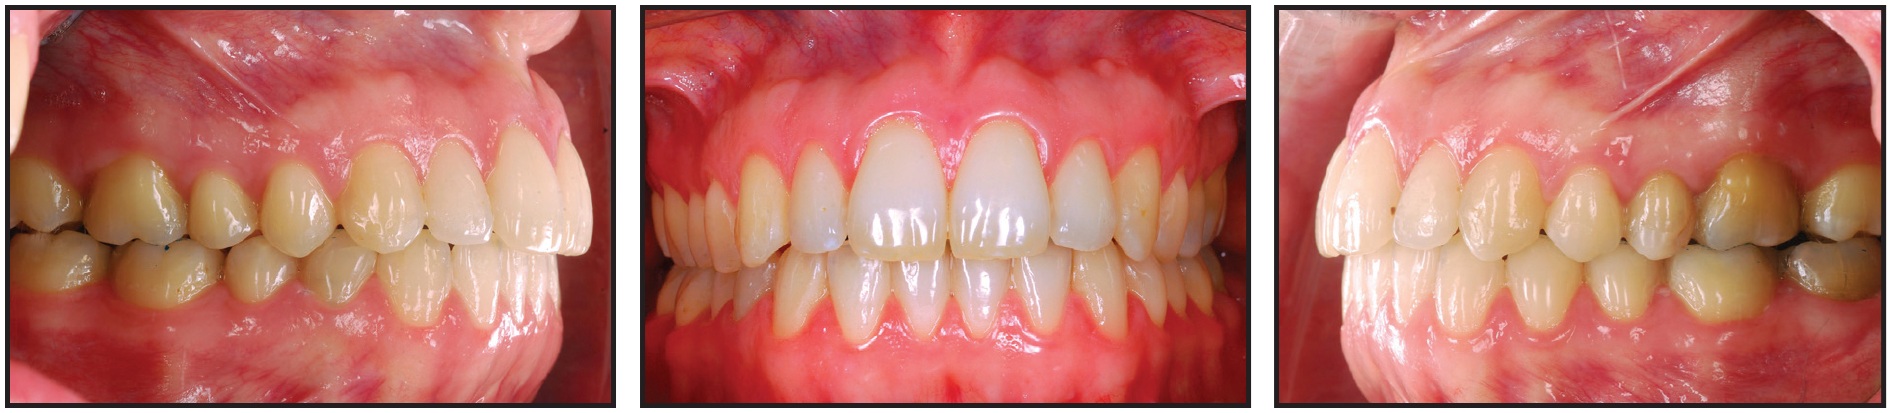

Orthodontic treatment was completed in 31 months, with the open bite closed and the incisor overlapping corrected. A canine and molar Class I relationship and normal function were achieved, with anterior and canine guidance (Fig. 8A). The treatment approach described here resolved the skeletal Class II pattern while intruding the posterior segments, allowing mandibular autorotation. Anterior intrusion during the second half of treatment improved the patient's facial appearance by achieving parallelism of the upper and lower occlusal planes and eliminating the gummy smile. Counterclockwise rotation of the mandible then reduced the lower facial height and increased the chin prominence, resulting in a more esthetic profile. Long-term stability was enhanced by the achievement of functional harmony among the orofacial muscles. The patient could close her lips without straining the mentalis muscle, and her open-mouth posture, which had caused mouth-breathing and a lower tongue placement, was alleviated.

Fig. 8 A. Patient after 31 months of treatment. B. Superimposition of pre- and post-treatment cephalometric tracings.

Superimposition of pre- and post-treatment cephalometric tracings confirmed the intrusion of the upper molars, along with slight retroclination and extrusion of the upper incisors (Fig. 8B). The mandibular plane angle was reduced from 28.8º to 28.0º with respect to the Frankfort plane. The ANB angle decreased from 7.0º to 5.4º. Consequently, there was a shift from the obvious skeletal Class II pattern to a skeletal Class I.

Results remained stable two years after the completion of treatment (Fig. 9).

Fig. 9 Patient two years after treatment.